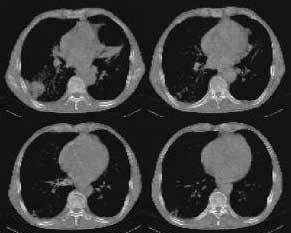

以下是引用woaixct在2006-6-23 12:15:00的发言:[br]第一张胸片示:右肺上叶为大片致密影占据,左肺上见大片致影及空洞性病灶并有液平;[br]第二张胸片示:左肺上叶致密影及空洞性病灶基本吸收,而右肺上叶之病灶有少许吸收改变;[br]ct片示:右上叶大片软组织密度,右肺门区至右肺上叶见巨大软组织块,内见支气管充气征,上纵隔右移,主气管及上叶支气受压变扁,中间支气管狭窄,左肺上叶空洞性病灶并有液平,左肺上叶尖后段见大片致密影,结合2张胸片考虑,ct片是4月份所摄,而不是6月份的片子;[br]结合2张胸片及ct片考虑:[br] 1.右中央型肺癌伴右肺上叶不张;[br] 2.左肺上叶尖后段炎性变及左肺脓肿;[br]第2张胸片提示:经过一个多月的不规则抗炎治疗,左肺上叶病灶及右肺上叶不张病灶基本吸收,而右肺占位无明显变化。

以下是引用jiangjing在2006-6-23 21:21:00的发言:[br]个人考虑还是两肺感染性病变可能大,主支气管及叶支气管是通畅的,并可见支气管气相;ct提示病变是以肺叶分布的,密度相对均匀;胸片可见有叶间裂下坠征,是不是考虑克雷伯杆菌感染可能.病人前后两张片比较病变是增多[应该考虑混合感染可能性大,右肺癌待排建议查痰及穿刺检查]